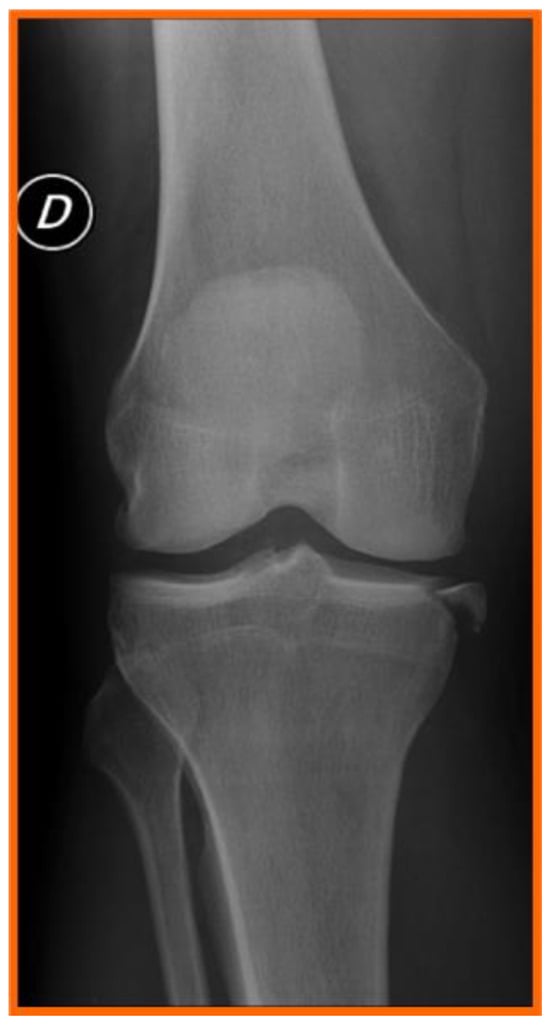

4.2. Clinical Evaluation of Combined MCL and ACL Injuries

4.3. Instrumental Evaluation

4.4. Magnetic Resonance Imaging (MRI) in the Diagnosis of ACL and MCL Injuries